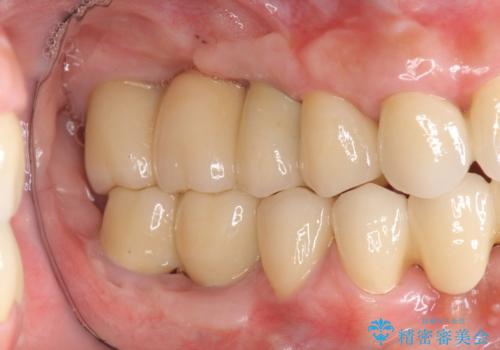

![[ 破折し大きく吸収した歯槽骨 ] 他院では難しいと言われたインプラント治療の症例 治療前](https://seimitsushinbi.jp/wp/wp-content/uploads/2024/10/073ce5e06775df372887a513b05b34d0-500x350.jpg?v=1729760111)

![[ 破折し大きく吸収した歯槽骨 ] 他院では難しいと言われたインプラント治療の症例 治療後](https://seimitsushinbi.jp/wp/wp-content/uploads/2024/10/7e00d9287463e80cbc3d4b87784b3d86-500x350.jpg?v=1729760167)